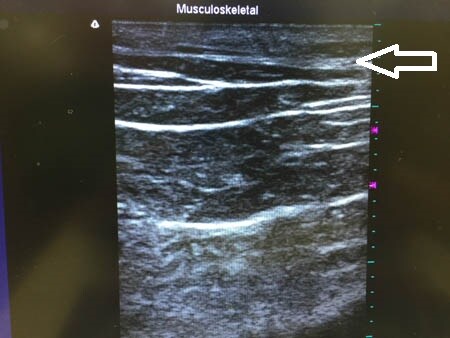

3Dタッチビュー(=超音波)で

皮下脂肪層の変化を見てみましょう。

上腹部。

上の画像の部分をつまんでみましょう。

下腹部も同様に見てみましょう。